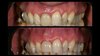

Patiente référée qui consulte pour des récessions tissulaires marginales associées à des sensibilités.

Un bilan parodontal est effectué puis on passe à la chirurgie gingivale.